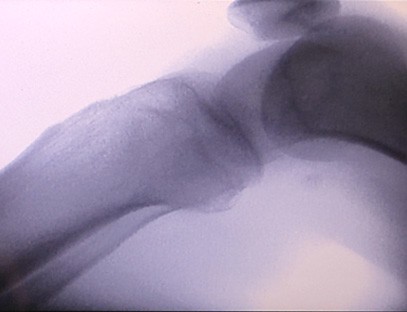

Il-Magni Ortopediċi tar-Raġġi X tagħna huwa prodott ta 'kwalità għolja li kien iddisinjat partikolarment għall-immaġini ortopediċi. Jista 'jintuża għad-dijanjosi u l-ippjanar tat-trattament ta' kundizzjonijiet ortopediċi varji, inklużi ksur, dislokazzjonijiet, artrite u tumuri fl-għadam. Hija mgħammra b'teknoloġija avvanzata tar-raġġi-X li tippermetti immaġini ta 'kwalità għolja b'espożizzjoni mnaqqsa għar-radjazzjoni. Il-magna għandha sistema ta 'immaġni b'riżoluzzjoni għolja u tista' taqbad immaġini ta 'kwalunkwe struttura tal-għadam b'ċarezza kbira.

Il-Magna Ortopedika tar-Raġġi X tagħna tista 'tintuża f'diversi speċjalitajiet mediċi, inklużi l-ortopedija, newroloġija, u mediċina ta' emerġenza. Ħafna drabi jintuża għall-osservazzjoni fluworoskopika ta 'għadam tar-riġlejn umani, Sptarijiet veterinarji u domestiċi, Trattament ta' feruti f'siti sportivi, bini, vapuri tal-oċean, żoni remoti u siti tal-kamp militari. Uħud mill-applikazzjonijiet kliniċi jinkludu:

1. Dijanjosi ta 'ksur, dislokazzjonijiet, u korrimenti oħra fl-għadam.